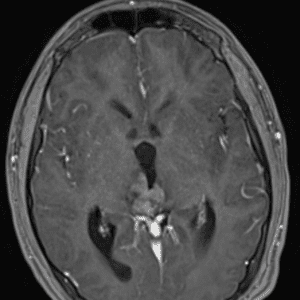

Case #7

Cerebellar metastasis